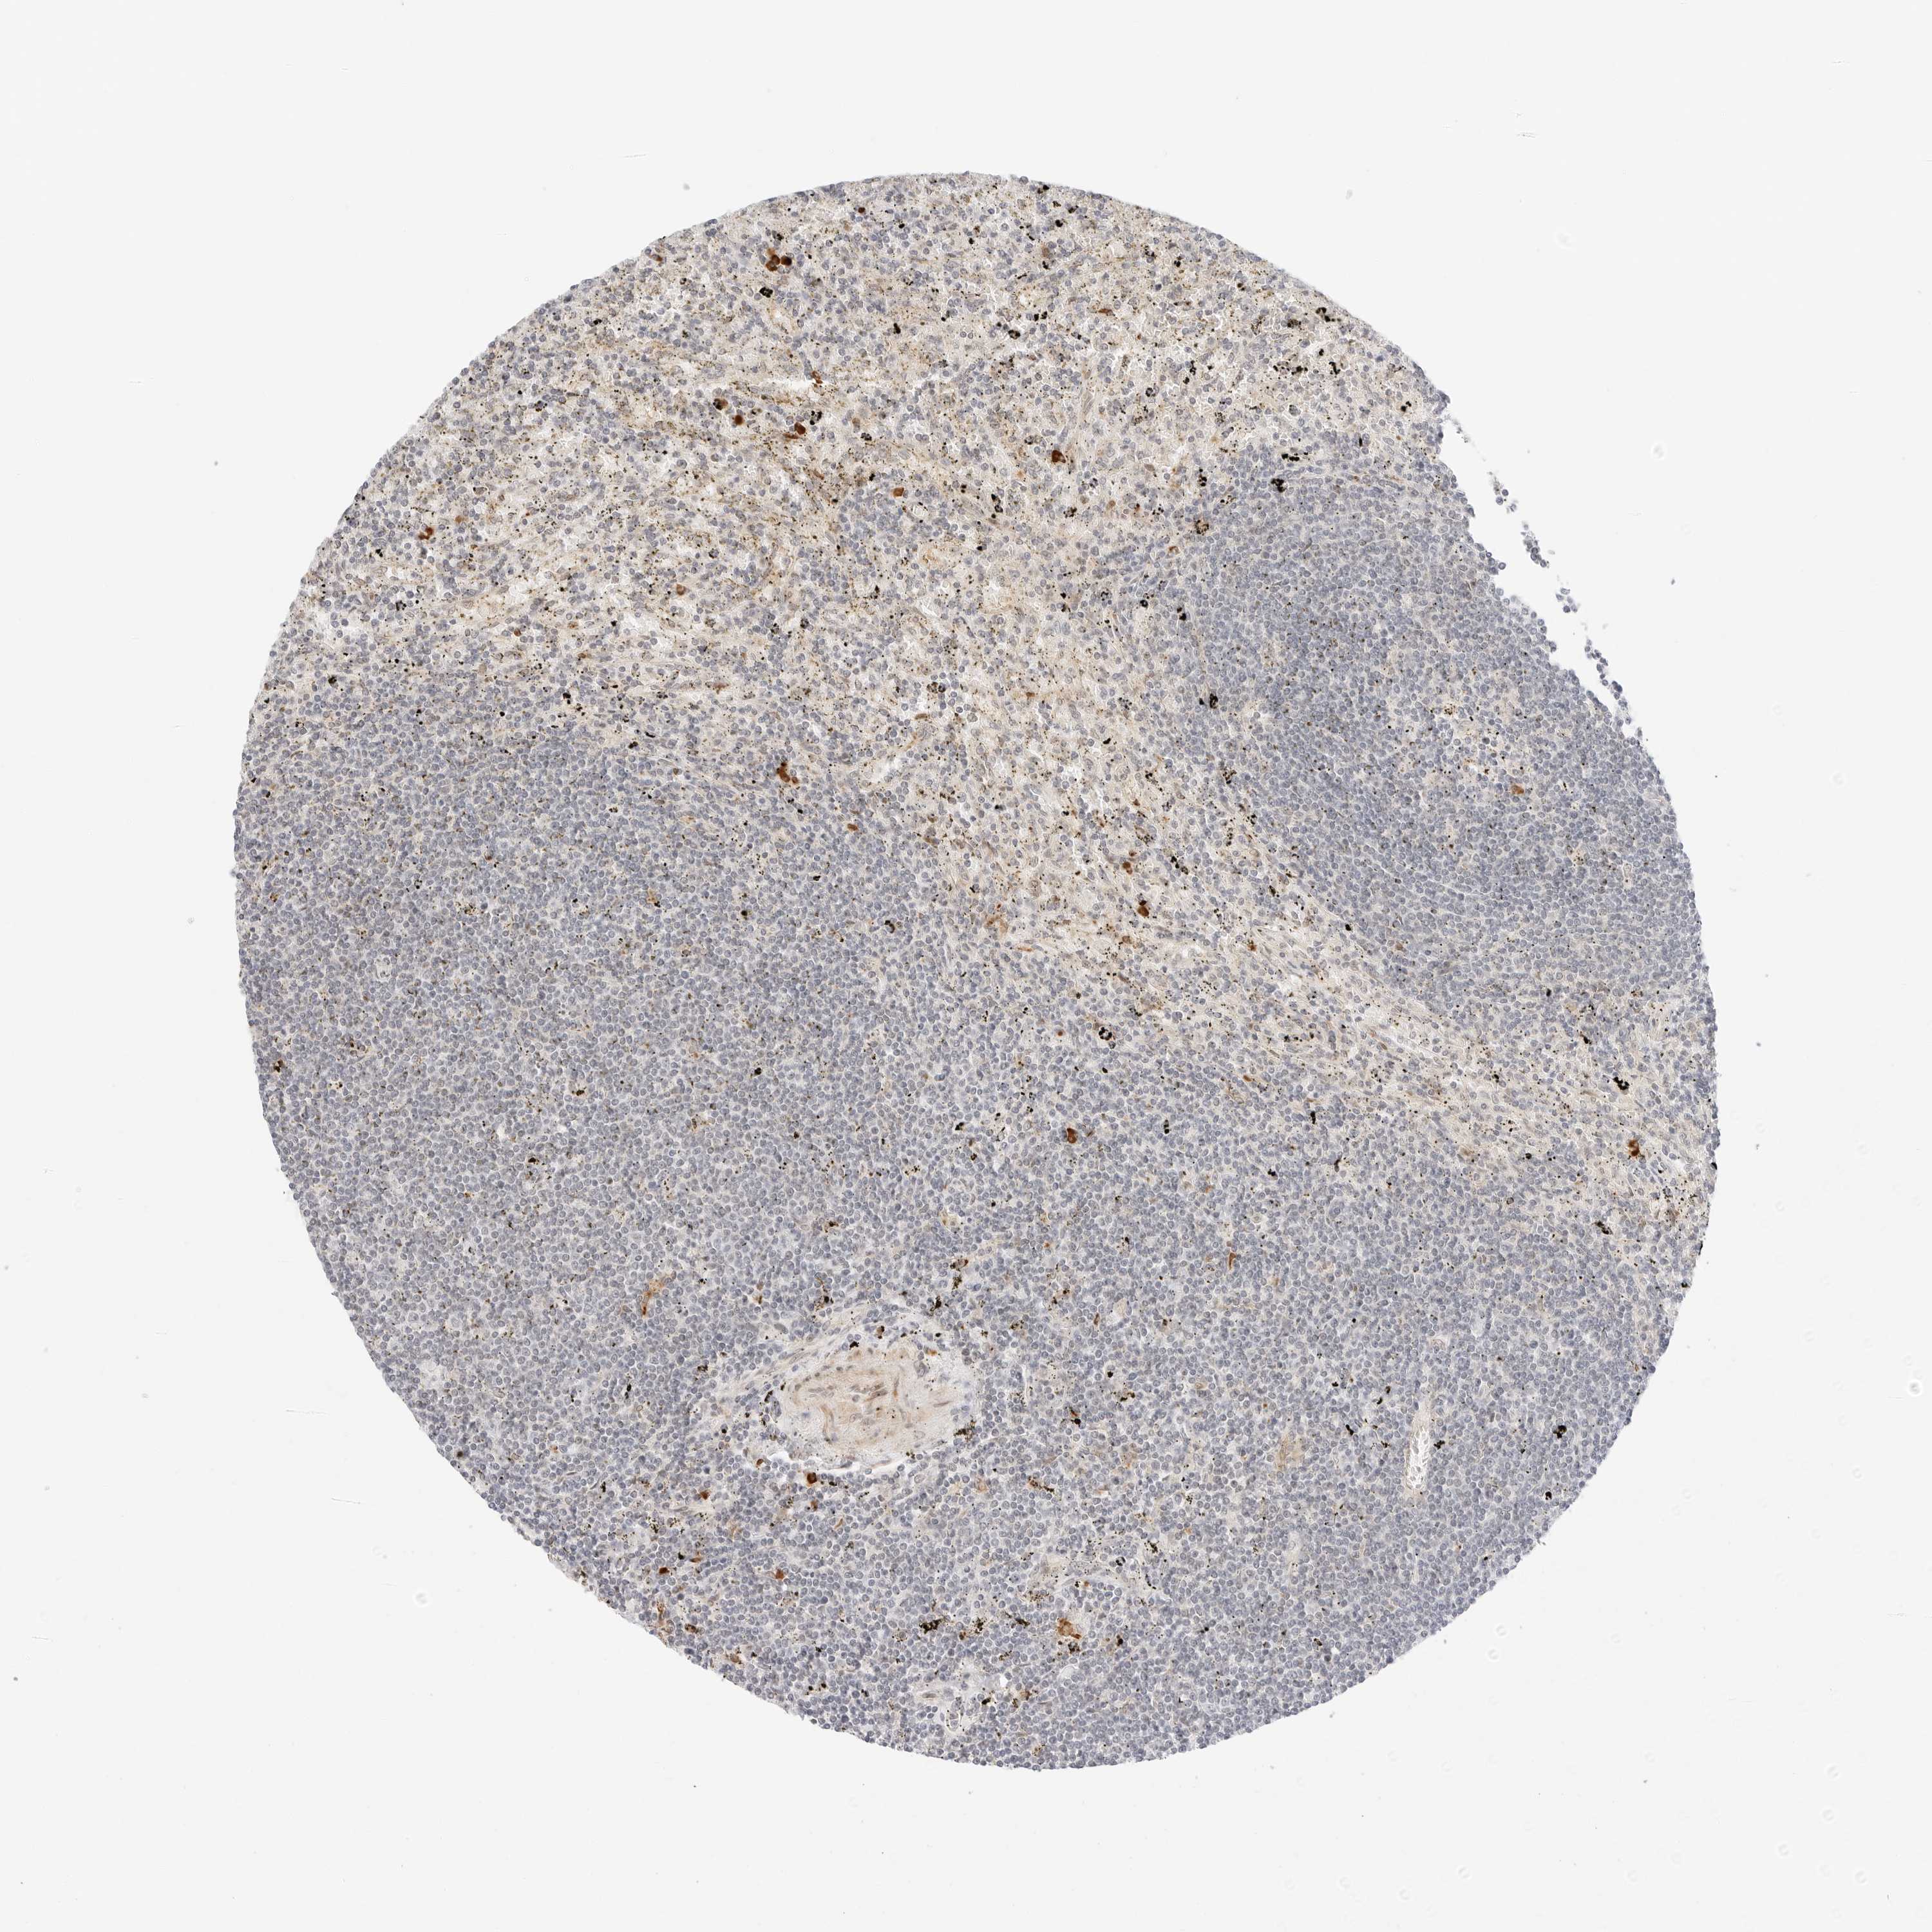

LYMPHOMA - Protein expressioni

A mouse-over function shows sample information and annotation data. Click on an image to view it in a full screen mode. Samples can be filtered based on level of antibody staining by selecting one or several of the following categories: high, medium, low and not detected. The assay and annotation is described here.

Antibody staining in the annotated cell types in the current human tissue is reported as not detected, low, medium, or high, based on conventional immunohistochemistry profiling in selected tissues. This score is based on the combination of the staining intensity and fraction of stained cells.

Each image is clickable and will lead to virtual microscopy that enables deeper exploration of all samples and also displays staining intensity scores, fraction scores and subcellular localization as well as patient and tissue information for each sample.

Antibody HPA027461

Staining

High

Medium

Low

Not detected

Intensity

Strong

Moderate

Weak

Negative

Quantity

>75%

75%-25%

<25%

None

Location

Nuclear

Cytoplasmic/membranous

Cytoplasmic/membranous,nuclear

Hodgkin's disease, NOS

Malignant lymphoma, non-Hodgkin's type, High grade

Malignant lymphoma, non-Hodgkin's type, Low grade